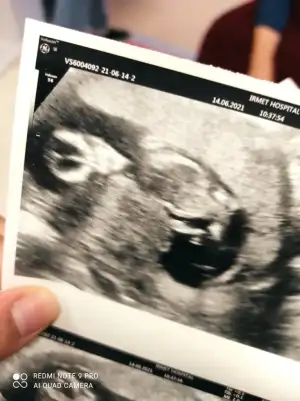

Erkek görünüyorIkra meyra merhaba 12+3 bakabilirmisiniz acaba bana da

Daha minik 11 12 13 haftalar olmalıTam olarak kaç haftada tahmin edebiliyorsunuz acababende merak ettimde atayım bakim inşallah görürsünüz

Erkek görünüyorMERHABA İyi Akşamlar,12 hafta ultrason görüntüsü bana da tahminde bulunabilirseniz çok Sevinirim![]()